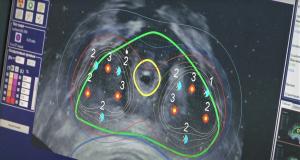

Радиотерапия

Лучевая терапия

Облучение является одним из основных методов в онкологической практике и применяется для многих видов опухолей и стадий как в самостоятельном плане, так и в сочетании с другими методами.